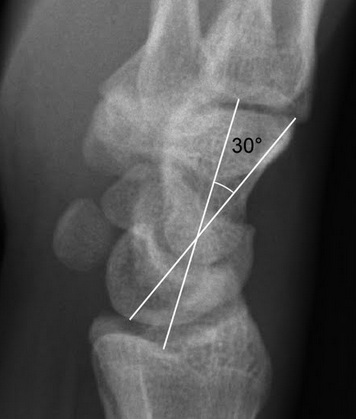

- Lateral view: Scapholunate angle >60 degrees

- Dorsal intercalated segment instability

- Dorsal angulation of lunate relative to radius resulting in capitolunate angle > 20°

- Seen as loss of the normal collinear arrangement of the capitate, lunate, and radius